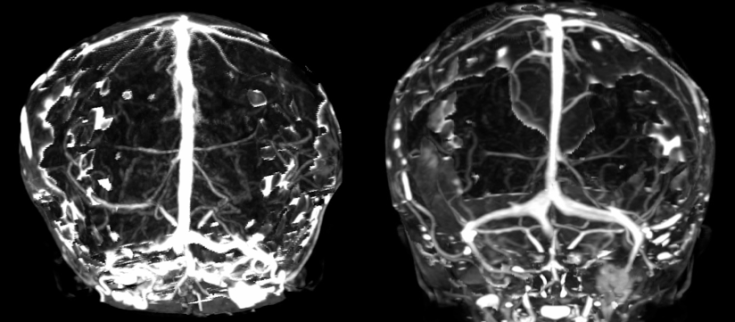

- l’IRM montre la compression cérébrale, la compression des sinus veineux et la circulation de suppléance par les veines trans-osseuses, l’engagement tonsillaire